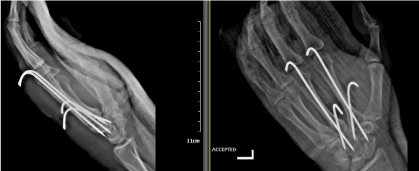

Multiple Carpometacarpal Joint Dislocation; a clinical image

Seyyed-Mohammad Qoreishi1, Hossein Mohebi2 and Seyyed-Mohsen Hosseininejad2,3

Traumatic fracture dislocations of second to fifth carpometacarpal (CMC) joints is a rare injury making up less than 1% of hand injuries [1]. Notifying the joint disruption could be difficult due to swelling and overlapping of bones.